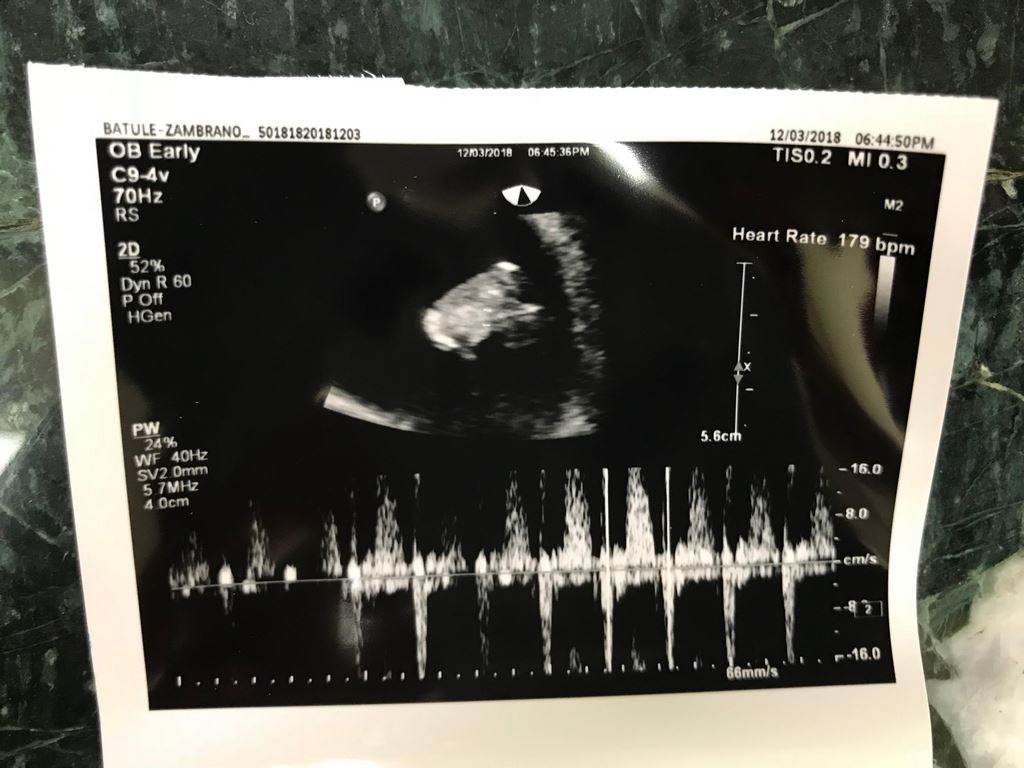

MERRY CHRISTMAS TO ALL FROM OUR FIRST GRANDAUGHTER EVELINA and her future sibling!